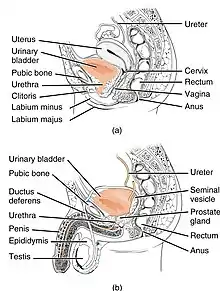

| Anatomy of the lower urinary tract and genital system. The top diagram shows the female urinary system, and the bottom shows the male urinary system. | |